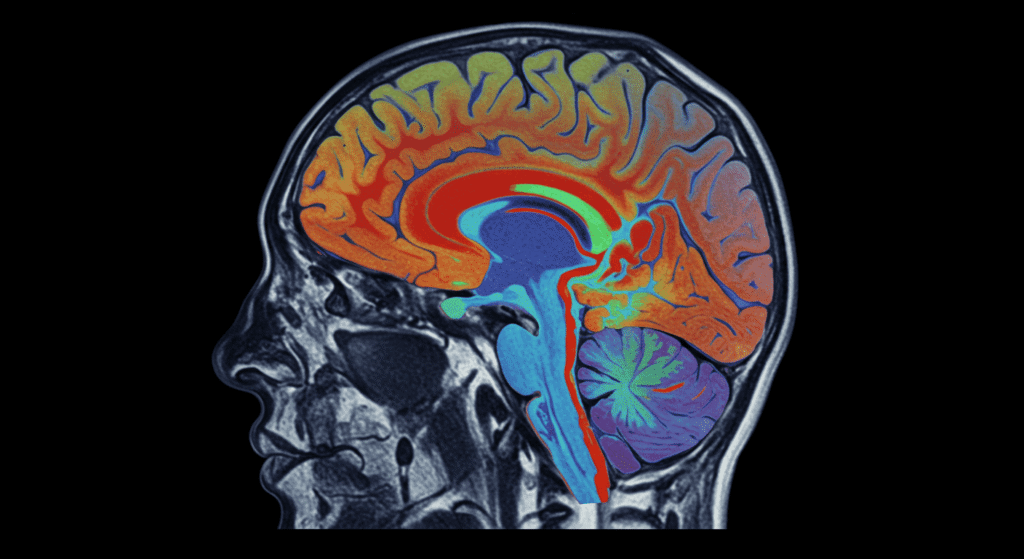

El interés por entender si los criminales, especialmente los homicidas, tienen cerebros distintos al resto de las personas, comenzó hace más de un siglo y sigue siendo objeto de estudio. Un gran avance llegó en los años 80 con la invención de la resonancia magnética funcional (fMRI), que revolucionó la manera de observar qué pasa dentro de la cabeza.

Durante años, Raine y su equipo analizaron los cerebros de 41 asesinos, y casi todos presentaron patrones similares: una actividad reducida en el córtex prefrontal, la zona encargada de controlar impulsos emocionales, y una sobreactivación de la amígdala cerebral, que es donde se generan las emociones intensas como la ira y el miedo.

Esto sugiere que los homicidas tienen cerebros más propensos a la ira y al enfado, pero con menos capacidad para controlar esos impulsos. En otras palabras, un desequilibrio entre la emoción y el control racional.